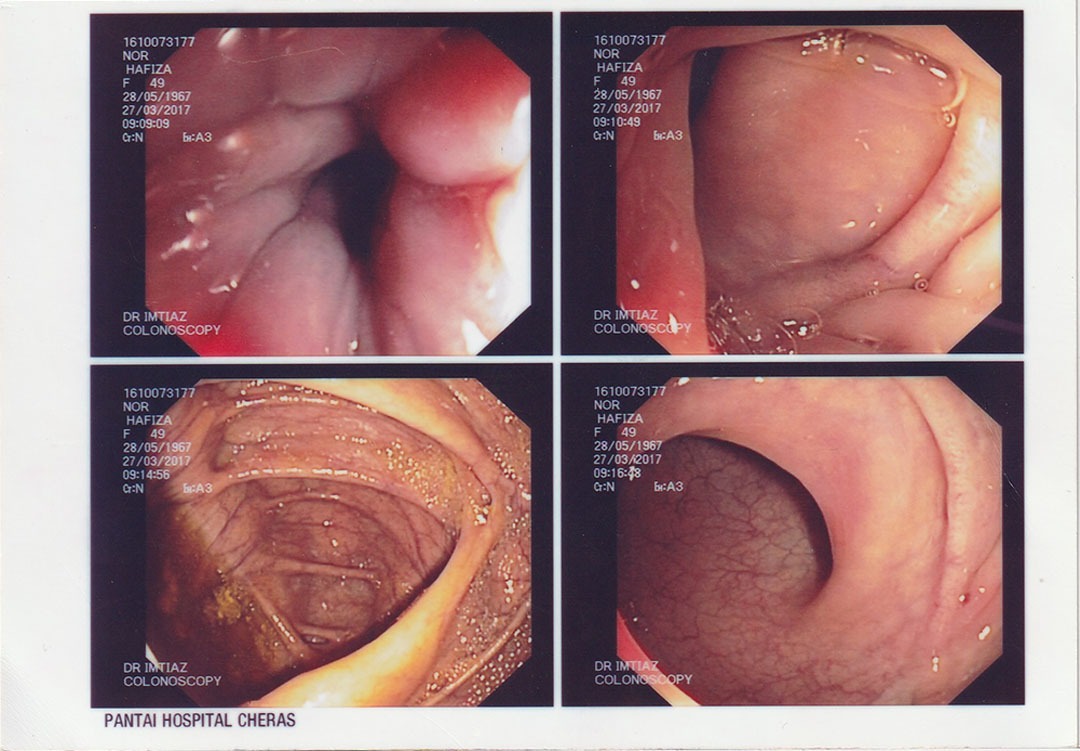

Pada tahun 2016, saya mula mengalami ketidakselesaan yang teruk pada bahagian perut, pergerakan usus yang tidak teratur, dan gejala membimbangkan yang mengganggu kehidupan seharian. Apabila menerima diagnosis serius mengenai kesihatan sistem pencernaan saya, dunia terasa gelap seketika. Saya bimbangkan masa depan suami dan anak-anak. Alhamdulillah, suami saya terjumpa risalah Ibnu Sina Wellness™ di surau dan mencadangkan agar saya mencubanya sebagai jalan sokongan ke arah pemulihan.

Saya memulakan perjalanan bersama Ibnu Sina Wellness™ pada Januari 2017 dengan penuh harapan. Hasilnya sungguh luar biasa! Dalam tempoh beberapa bulan, pemeriksaan menunjukkan sistem dalaman saya beransur-ansur pulih dengan sendirinya. Menjelang 2018, pemerhatian klinikal menunjukkan saluran pencernaan saya telah kembali ke tahap yang sangat sihat dan cergas. Pendekatan ini bukan sahaja menyokong pemulihan fizikal, malah menguatkan kesejahteraan emosi dan spiritual saya.